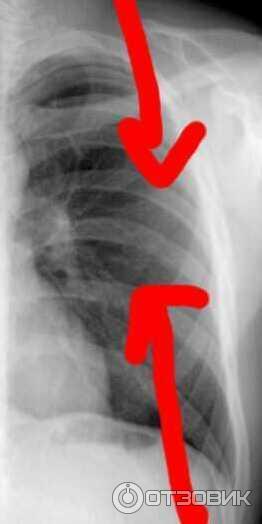

Медицина и диагностика: Аномалии ребер на рентгене